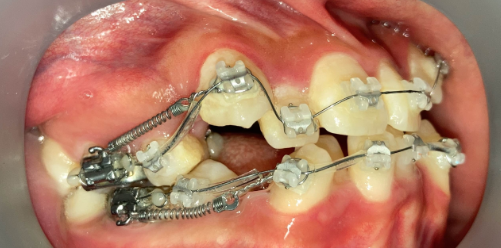

抜歯矯正1年後の口腔内|奈良の矯正歯科

治療1年後

他院で非抜歯矯正を受けたものの、口元の突出感が改善せず来院。精密検査の結果、上下4本の抜歯が必要と判断し、ワイヤー矯正でやり直しました。